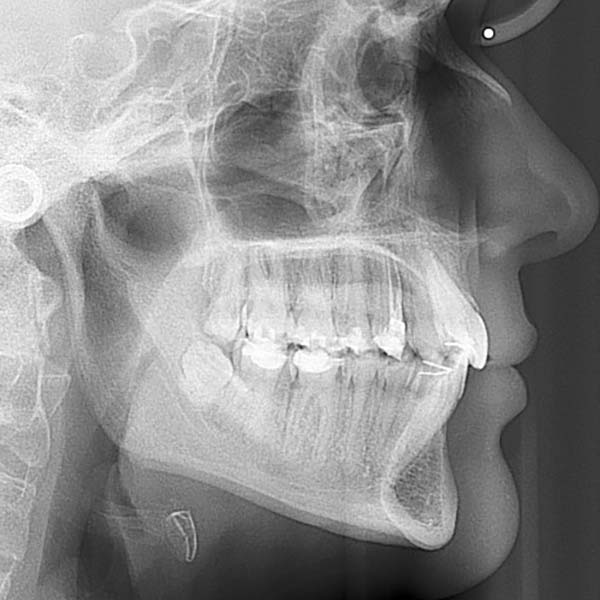

This lady visited me complaining that her upper teeth cover the lower ones excessively.

Examination revealed a severe deep bite, covering almost all parts of the lower teeth, in addition to a severe backward tilt in her upper front teeth, which affected the beauty of her smile.

Fortunately, this woman did not suffer from problems in her joint before the date of her visit to the clinic, Since these cases usually persist for a long time, causing pain and problems in the joint, (due to the patient’s need to open his mouth widely, each time he wants to free his lower jaw from the upper teeth)